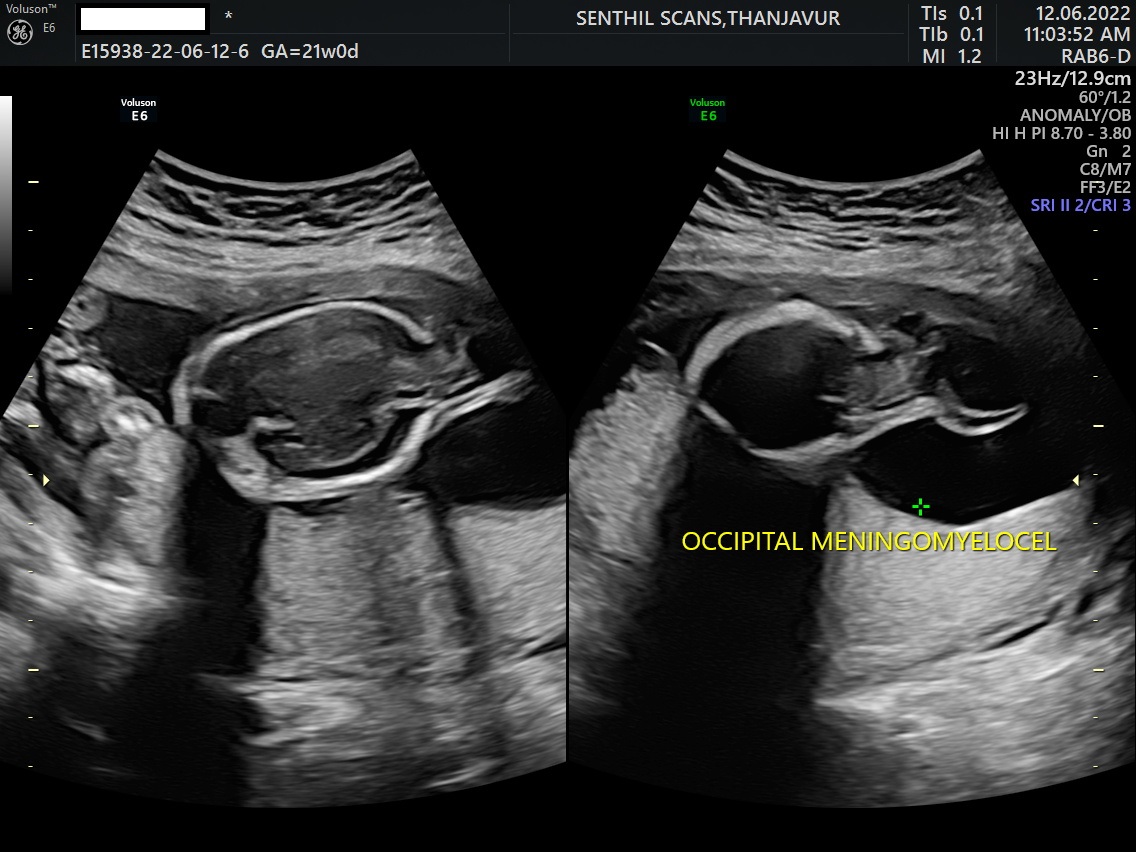

Meckel-Gruber Syndrome